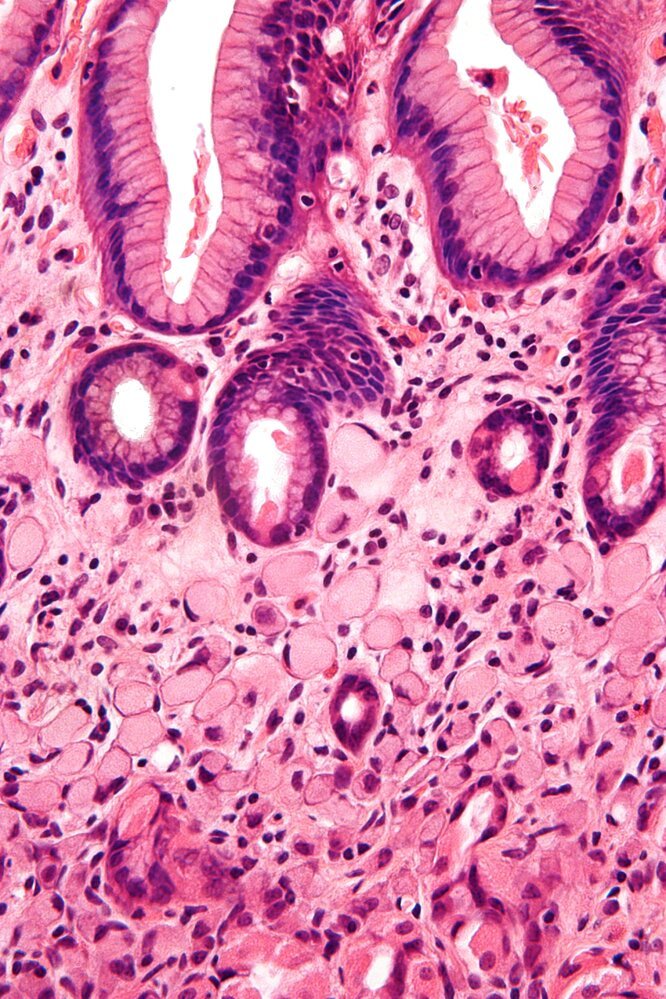

Gastric Adenocarcinoma

There are atypical cells forming glandular structures (green circles) of various sizes with intraluminal debris.

These findings are consistent with gastric adenocarcinoma.